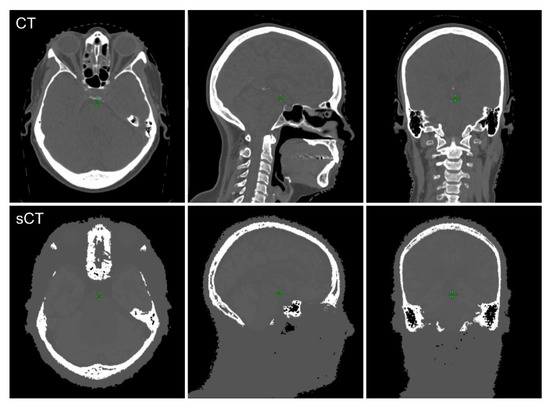

3.1. Bone Segmentation and Comparison of HU Values